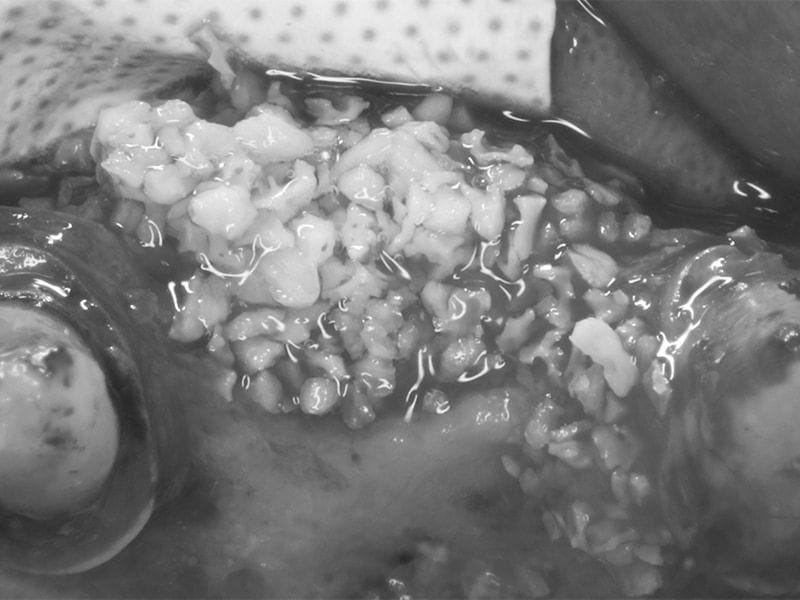

在舒眠鎮靜下執行補骨手術,置放人工骨粉與再生膜,手術順利。在半年後我們依照最佳的假牙設計位置製作手術導板,從再度拍攝的電腦斷層影像我們可以看到,骨量寬度明顯增加。

植牙前補骨手術,置入人工骨粉 補骨後覆蓋再生膜 手術導板可顯示最佳植牙位置,同時模擬未來鄰

牙的牙齒設計與牙齦位置